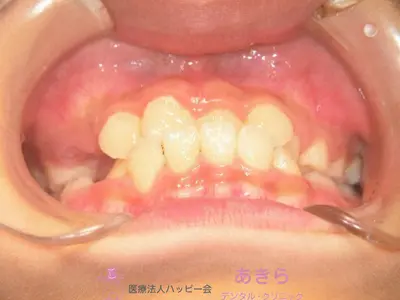

初診時

case-001-1